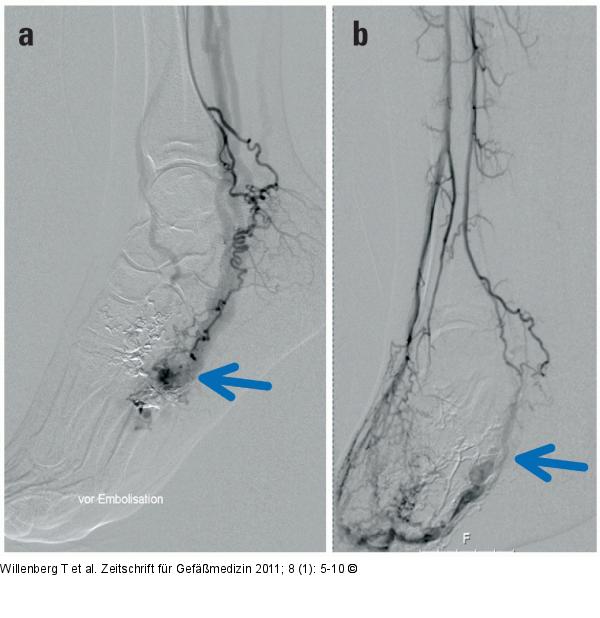

Abbildung 7a-b: Angiographisches Bild Angiographisches Bild (a) vor und (b) nach Ethanolembolisation. Der Nidus (Pfeil) mit Abstrom nach proximal ist nach der Embolisation ausgeschaltet. |

Angiographisches Bild (a) vor und (b) nach Ethanolembolisation. Der Nidus (Pfeil) mit Abstrom nach proximal ist nach der Embolisation ausgeschaltet. |